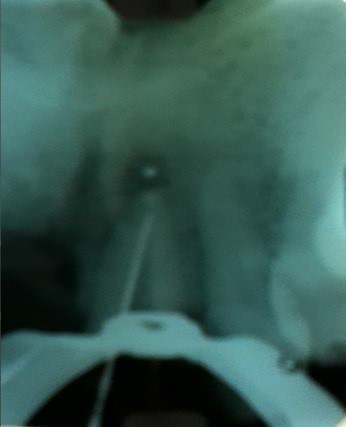

Devido à persistência do exsudato via canal, optou-se pela realização da obturação endodôntica, seguida de tratamento cirúrgico complementar (apicectomia) com retrobturação com MTA.

Decidiu-se, então, pela apicectomia com tratamento endodôntico transcirúrgico, usando MTA como cimento obturador. Foi realizada uma apicectomia cuidadosa, conservando assim, o máximo possível de estrutura dental.

No controle pós-operatório de sete dias, o paciente não apresentava sintomatologia que fosse incompatível com o ato cirúrgico realizado, sendo que a cicatrização se apresentava normal. Tal quadro persistiu por todo o período de acompanhamento, durante um ano, uma vez que a radiografia de um ano após o tratamento revelou neoformação óssea na região, comprovando o sucesso do caso.